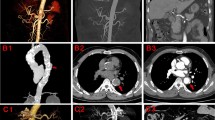

DURING a long-term study on the general biology of the California sea-lion, Zalophus californianus (Lesson), it became evident that degenerative diseases associated with ageing are very common in this species. Therefore, a study of the heart and aorta was undertaken.